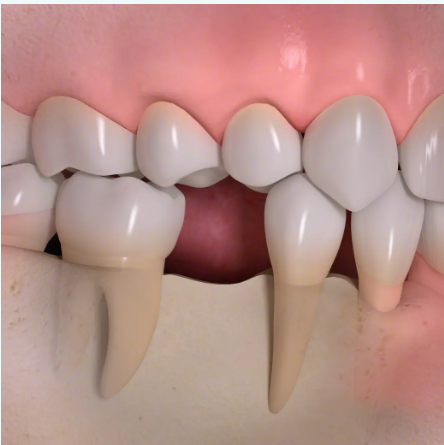

歯を失ったままにしておくと、以下のような見た目・機能・精神面での悪影響が広がっていきます:

■骨が吸収され、歯ぐきが痩せて老けて見える

■隣の歯や噛み合う歯が移動し、噛み合わせが悪くなる

歯を失ったままにしておくと

• 1

歯根が失われると、骨に伝わる力がなくなり、歯を失った部分の骨がやせていきます。

• 2

歯の喪失によって歯が移動し、歯並びがかわってしまう場合があります。

• 3

歯の喪失によって、見た目が悪くなります。

• 4

骨の喪失によって顔の輪郭が変わってしまいます。